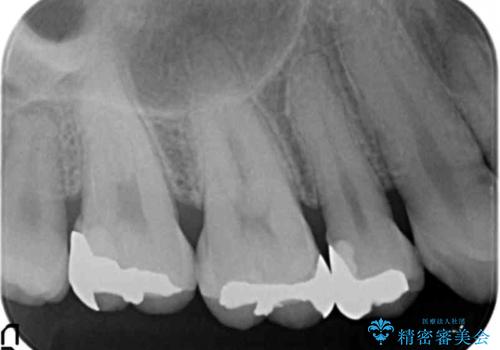

食べ物が詰まる 親知らずが原因の虫歯再発

- 銀歯と親知らずの間に毎回食べ物が挟まることを自覚していたが、放置した結果虫歯が再発し検診で発覚し治療を行うこととなりました。

原因となる親知らずや周囲の虫歯は、出産後に行う予定です。